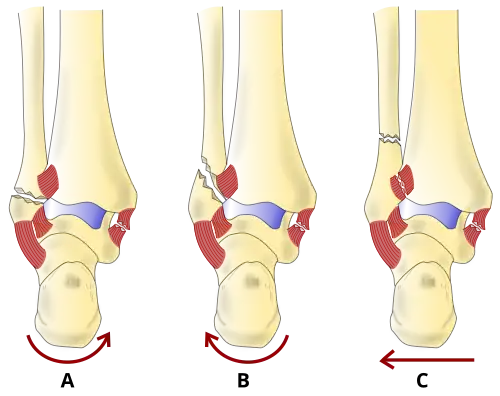

There are several classification schemes for ankle fractures. Out of the following, the Lauge-Hansen and Danis-Weber classification systems are most commonly used.[9]

- The Lauge-Hansen classification categorizes fractures based on the mechanism of the injury as it relates to the position of the foot and the deforming force (the most common type is supination-external rotation)

- The Danis-Weber classification categorizes ankle fractures by the level of the fracture of the distal fibula (type A = below the syndesmotic ligament, type B = at its level, type C = above the ligament), with use in assessing injury to the syndesmosis and the interosseous membrane